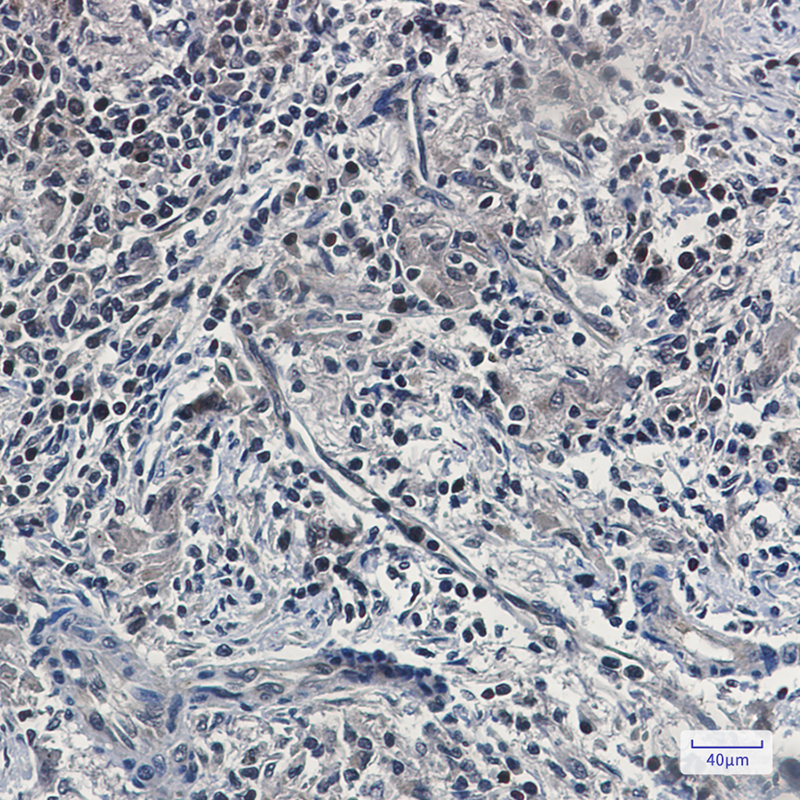

分类: 科研抗体货号: P20826别名: KIAA0723; Matr3; Matrin3; MPD2; VCPDM应用: WB,IHC,IF反应种属: Human